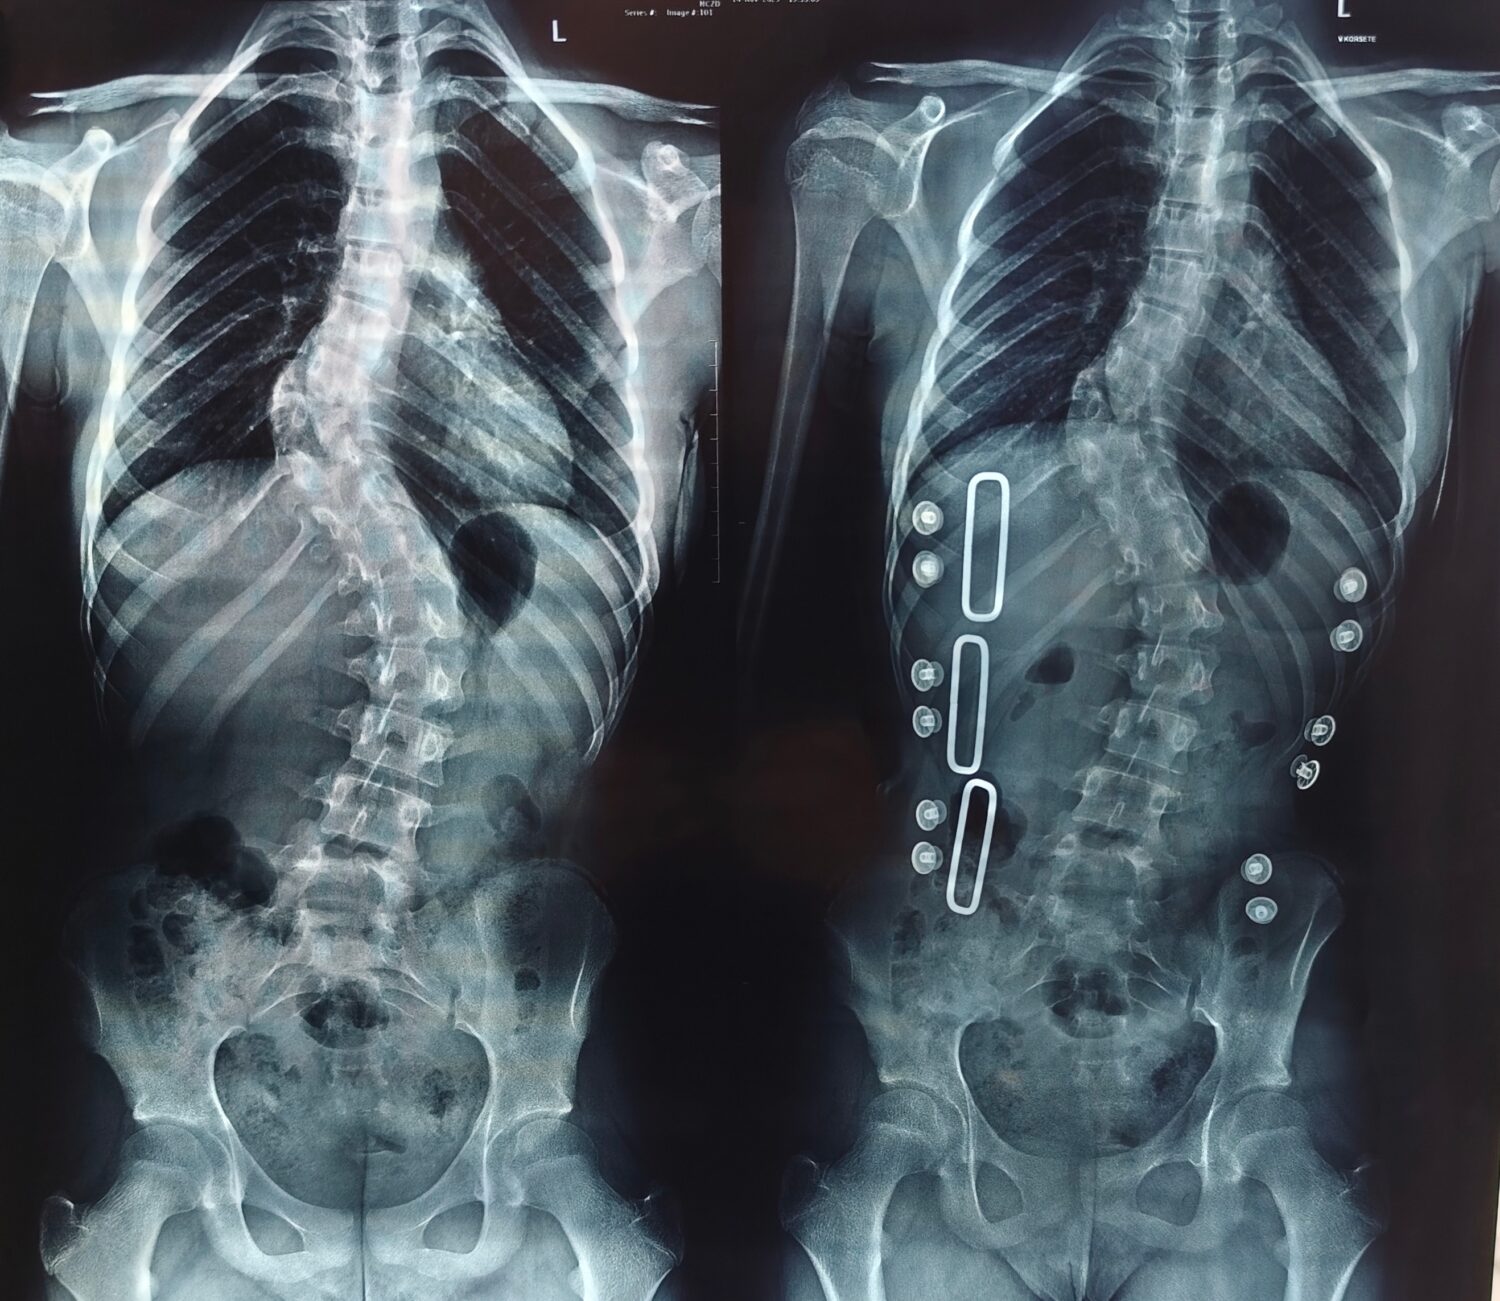

Недавно девочка опять была на приеме у врача, и ей снова сделали рентген. Результат изменений за год очень тревожный — искривление увеличилось на семь градусов. Это много — обычно сколиоз не прогрессирует так быстро. Надиря говорит: «Врач посмотрел наши результаты и сказал: «Корсет и зарядка не помогают, мучить девочку нет смысла, нужна операция. Срочно»».

— Нам рассказали, как будет проходить операция, — объясняет Надиря. — На позвоночник установят особую металлоконструкцию. Она содержит в себе шурупы, крюки. Ставится на позвоночник. Разрез делают сзади. С помощью такой конструкции деформация исправляется, и позвоночник фиксируется в правильном положении. Конструкцию удалять не надо, она остается на всю жизнь.

Так как Алия еще совсем юная и продолжает расти, ей нужна специальная подвижная металлоконструкция, растущая вместе со скелетом и позвоночником. К сожалению, по ОМС такая металлоконструкция не предоставляется. И девочке нужна наша помощь.